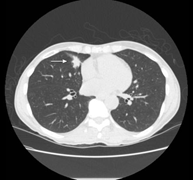

在形态上,肺结节分为实性(如图1)或亚实性;亚实性结节又细分为大名鼎鼎的纯磨砂玻璃结节,即pGGO(无实性成分)(如图2)和部分实性结节(磨玻璃加实性成分)(如图3)。

图1 实性结节(真实美)